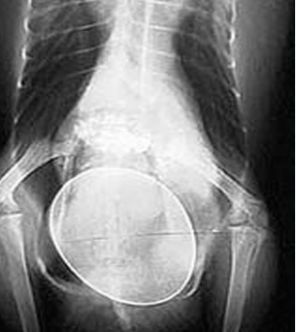

سعی نکنید خودتان

تخم مرغ

را خارج کنید، چراکه ممکن است باعث آسیب به پرنده، فلجی و حتی مرگ شوید. در عوض پرنده را نزد دامپزشک ببرید. رادیوگرافی برای بررسی محل تخم و هرگونه مورد غیر طبیعی در سایز تخم انجام می شود. پس از آن دامپزشک سعی می کند به طور طبیعی تخم را خارج سازد؛ به پرنده کلسیم و مقدار زیادی مایعات داده می شود، در محیط گرم نگهداری می شود و با گرما و لوبریکنت تخم خارج می شود